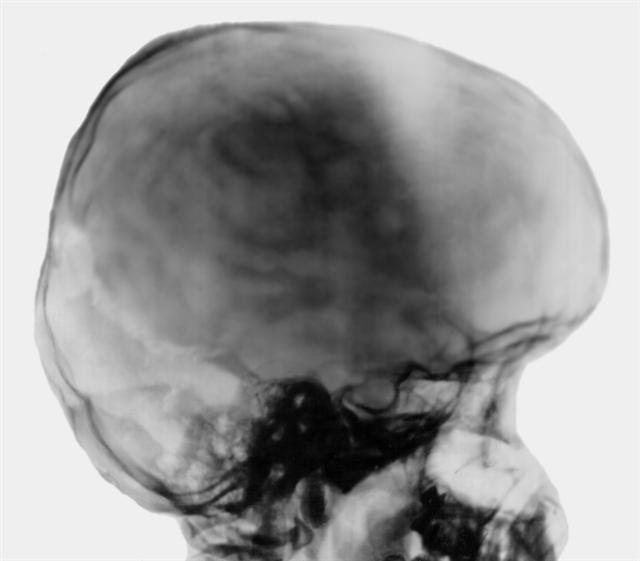

Рис. 1. Краниограмма ребенка 13 лет с окклюзионным синдромом (окклюзия в области водопровода мозга): гидроцефальная форма черепа, увеличение его размеров, истончение костей, сглаженность дуг свода, углубление черепных ямок, опущение центральной части средней черепной ямки вместе с турецким седлом; резкое растяжение и зияние швов, особенно коронарного; в правой половине лямбдовидного шва — участок резорбции кости; резкое углубление и опущение борозды поперечного синуса; увеличение турецкого седла, расширение его входа и укорочение спинки.